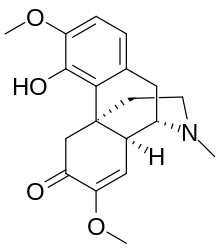

Structures

Structures of Morphine family

| Morphine family | ||||

|---|---|---|---|---|

14-Hydroxymorphine 14-Hydroxymorphine |

2,4-Dinitrophenylmorphine 2,4-Dinitrophenylmorphine |

6-Methyldihydromorphine 6-Methyldihydromorphine |

6-Methylenedihydrodesoxymorphine 6-Methylenedihydrodesoxymorphine |

6-Acetyldihydromorphine hydrochloride 6-Acetyldihydromorphine hydrochloride |

Azidomorphine Azidomorphine |

Chlornaltrexamine Chlornaltrexamine |

Chloroxymorphamine Chloroxymorphamine |

Desomorphine Desomorphine (Dihydrodesoxymorphine) |

Dihydromorphine Dihydromorphine |

Ethyldihydromorphine Ethyldihydromorphine |

Hydromorphinol Hydromorphinol |

Methyldesorphine Methyldesorphine |

N-Phenethylnormorphine N-Phenethylnormorphine |

6-nicotinoyldihydromorphine 6-nicotinoyldihydromorphine |

RAM-378 RAM-378 | ||||